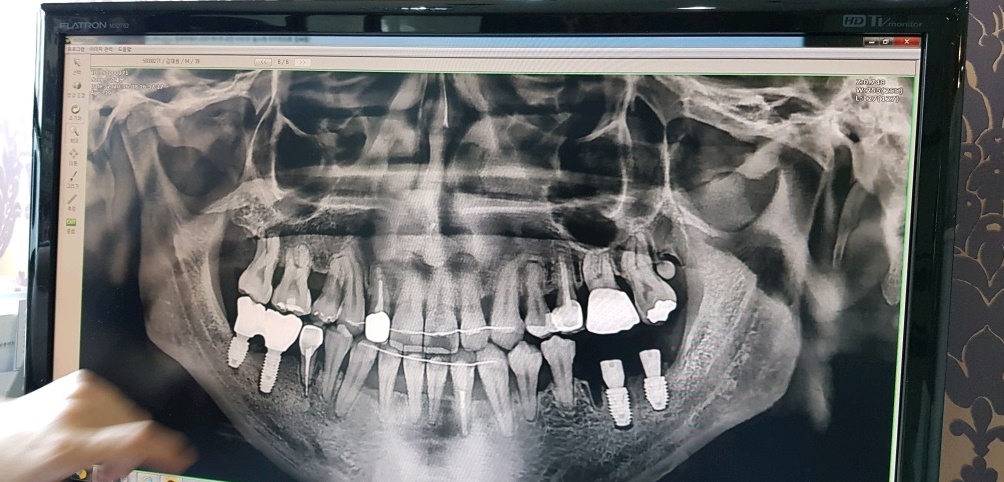

3년6개월에 거쳐 모든 과정이 끝난 지금의 내 치아상태인데

상악은 확실히 바뀐게 보이긴 한다..

그런데 밑의 앞쪽 치아들 중 한 치아는 강제로 이동되서 약간 비스듬히 뿌리가 잡혀있는게 보인다.

아마도 유지장치가 없다면 이 치아가 다시 원래자리로 돌아가겠지...